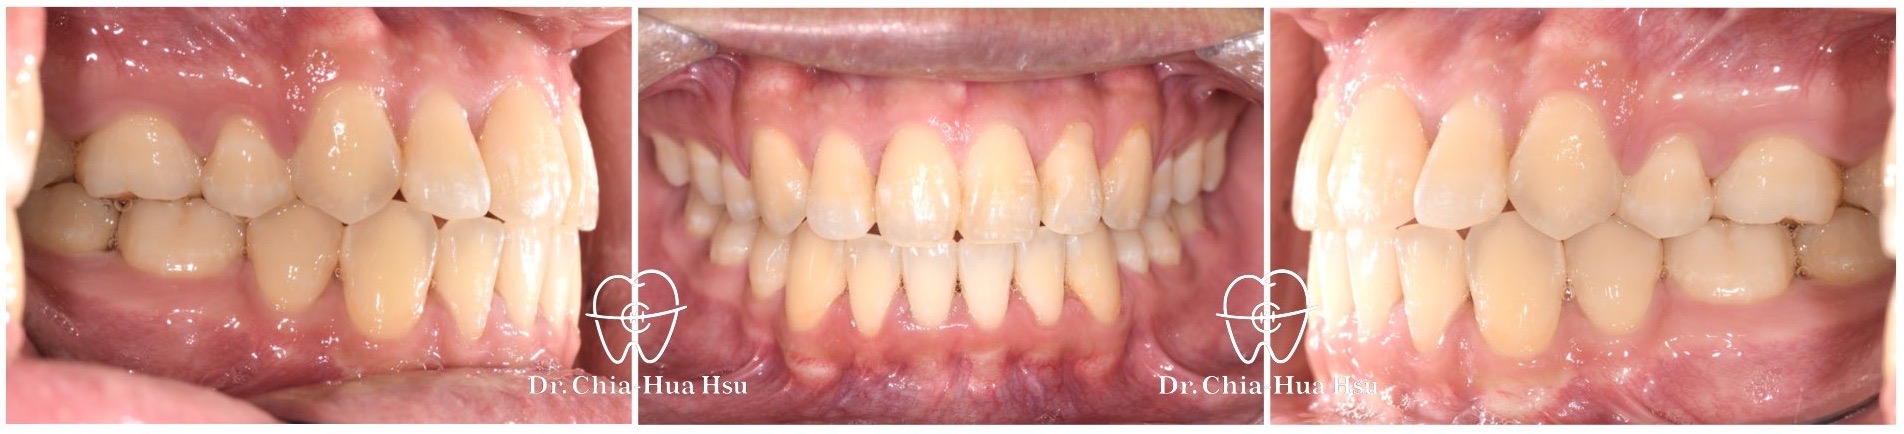

- 病患主訴:牙齒排列不整齊、側門牙躲在後面、嘴唇有點凸。

- 問題分析:患者是標準的骨骼一類咬合(Skeletal Class I)伴隨齒列擁擠以及嘴唇微凸。

- 治療結果:齒列排齊,嘴凸也有顯著改善,甚至下巴輪廓更明顯。

治療前

治療後